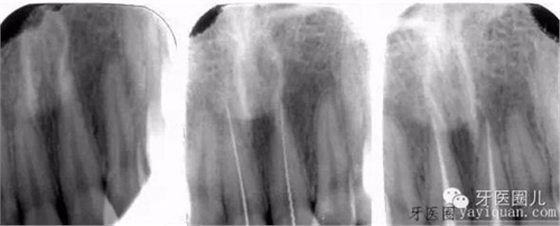

前牙折斷的前牙長(zhǎng)可以一次性完成治療:

患者外傷11 21簡(jiǎn)單冠折,選擇一次法完成冷牙膠充填3天后行樁修復(fù)。

一次法充填后最嚴(yán)重的疼痛發(fā)生在治療后24小時(shí)內(nèi),也有文獻(xiàn)說(shuō)是6-8個(gè)小時(shí),隨后患者反應(yīng)會(huì)大大減輕,與多次法比較治療的并發(fā)癥和成功率沒(méi)有差別,這個(gè)病例次日電話回訪患者患者無(wú)不適。

個(gè)人介于器械和時(shí)間原因,一次法只做適應(yīng)癥范圍內(nèi)前牙,后牙基本都是2-3次完成治療。